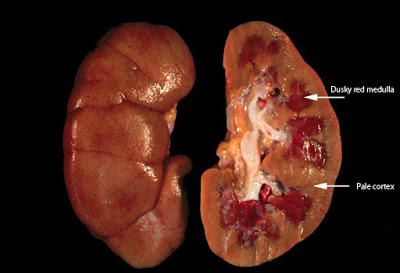

Η ONB είναι μια ξαφνική απώλεια της νεφρικής λειτουργίας. Αυτό δεν σημαίνει ότι οι νεφροί έχουν υποστεί ζημιά εφόσον η ΟΝΒ, ανάλογα με την αιτία, είναι συνήθως παροδική και αναστρέψιμη. Μπορεί όμως να οδηγήσει σε «οξεία νεφρική ανεπάρκεια» ή και «απώλεια τις νεφρικής λειτουργίας». Ο όρος «ουραιμία» χρησιμοποιείται για να περιγράψει ασθενείς με ανεπάρκεια νεφρικής αποβολής της ουρίας και των άλλων ουσιών με αποτέλεσμα την συσσώρευσή τους στο αίμα και την έναρξη εμφάνισης μεταβολικών επιπλοκών.